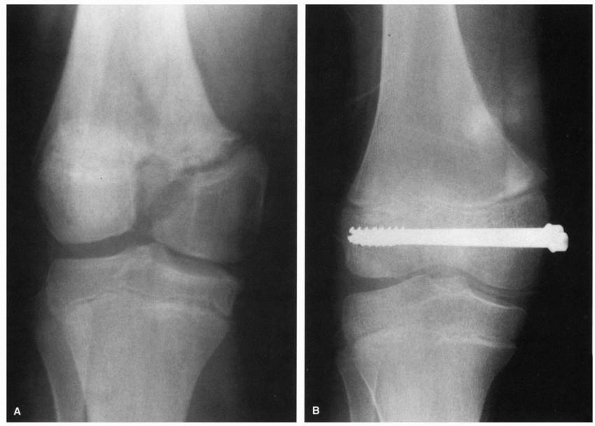

FIGURE 23-9 A.

Salter-Harris type III fracture-separation of the distal femur. Note the vertical fracture line extending from the physis distally into the intercondylar notch with displacement. B. After reduction and fixation with two compression screws extending transversely across the epiphyseal fragments. Note closure and healing of the vertical fracture line in the epiphysis, with restoration of the articular surface. |

FIGURE 23-10 A. Comminuted Salter-Harris type IV fracture of the distal femur in a 14-year-old boy involved in a motor vehicle accident. B. Six months after open reduction and internal fixation with cannulated screws in the metaphysis and epiphysis

|